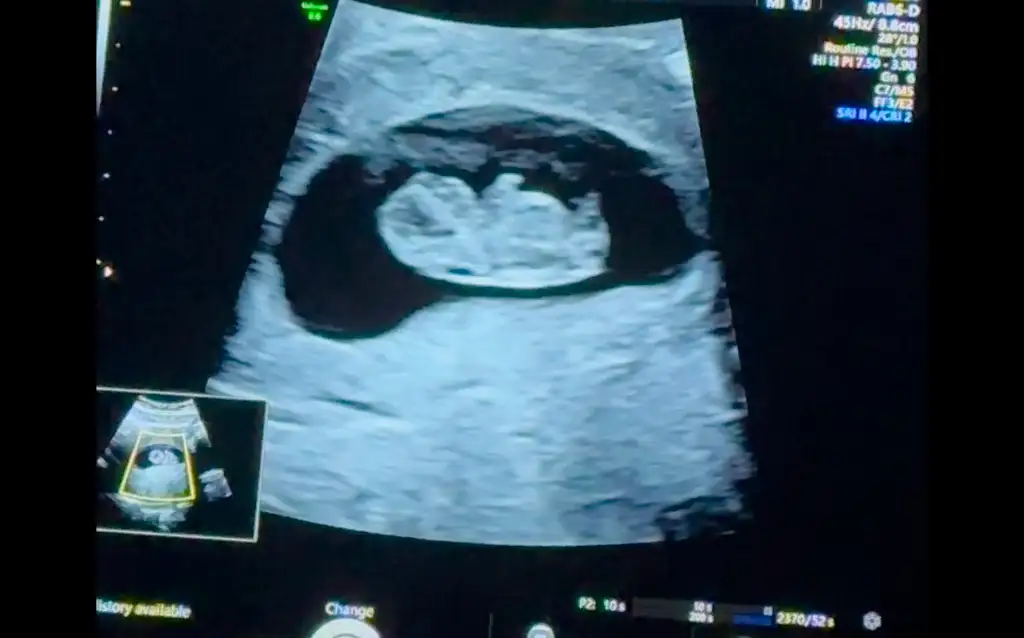

Ben de bir tahmin alabilir miyim minik kurbağam için :) 8+4 idi burada. Biz anne-baba olarak erkek hissediyoruz ama etrafımızdaki herkes kız hissediyor 🫠